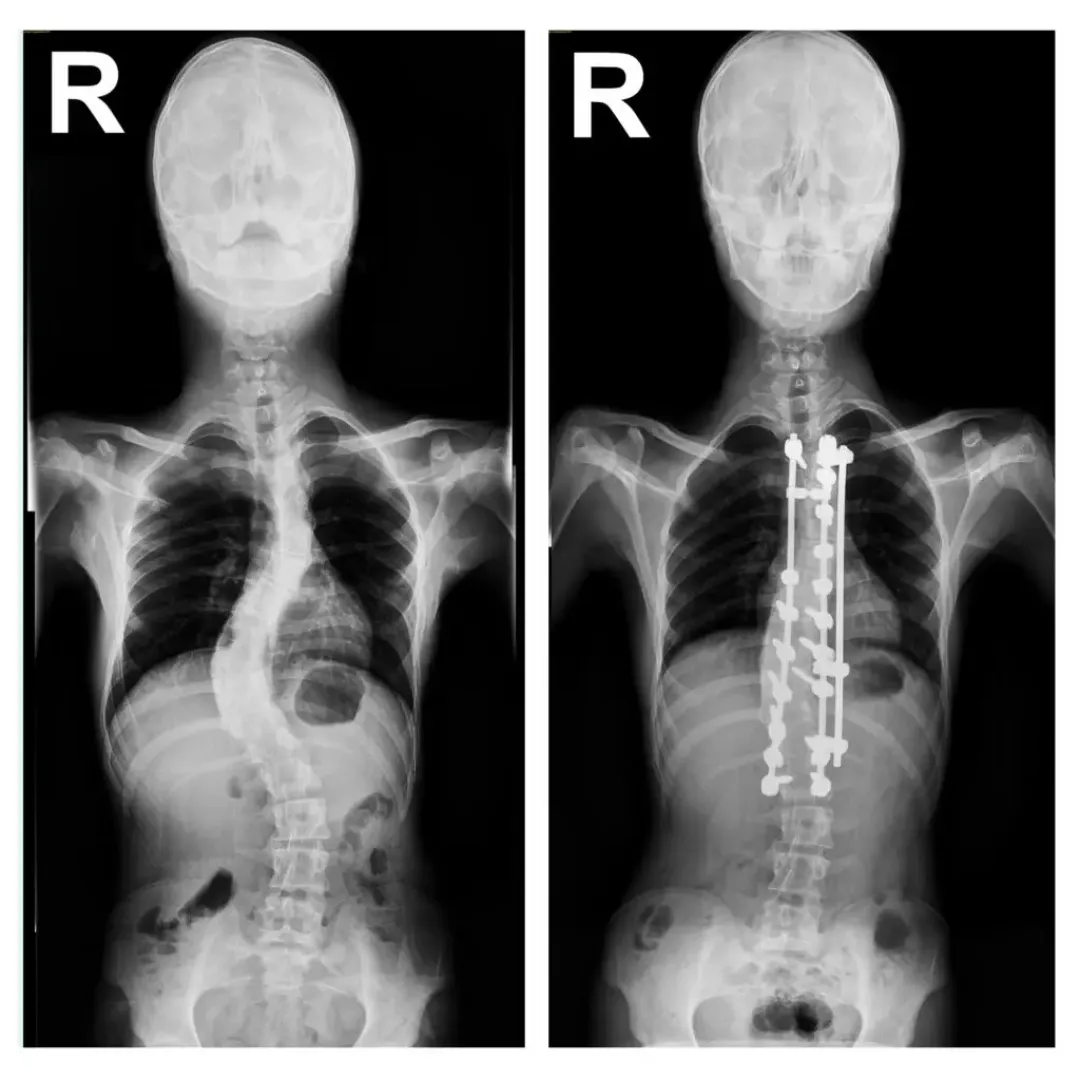

Cranio-Technology

Cranio-Technology

3D Skull Reconstruction

Advanced cranioplasty using customized titanium mesh implants to restore protection and aesthetic symmetry to the skull.